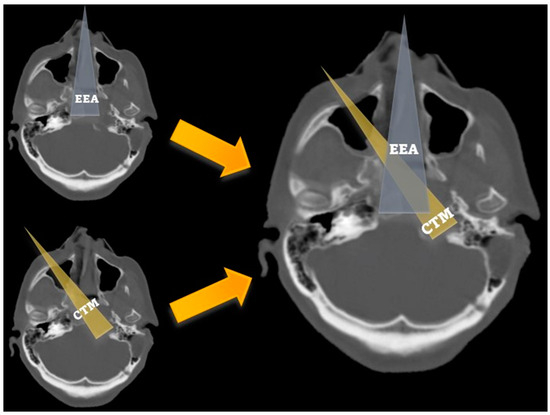

2.2. Surgical Technique

- The maxillary step